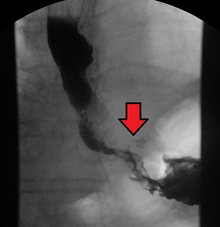

Although an occlusive tumor may be suspected on a barium swallow or barium meal, the diagnosis is best made with an examination using an endoscope. This involves the passing of a flexible tube with a light and camera down the esophagus and examining the wall, and is called an esophagogastroduodenoscopy. Biopsies taken of suspicious lesions are then examined histologically for signs of malignancy.

Additional testing is needed to assess how much the cancer has spread (see #Staging, below). Computed tomography (CT) of the chest, abdomen and pelvis can evaluate whether the cancer has spread to adjacent tissues or distant organs (especially liver and lymph nodes). The sensitivity of a CT scan is limited by its ability to detect masses (e.g. enlarged lymph nodes or involved organs) generally larger than 1 cm. Positron emission tomography is also used to estimate the extent of the disease and is regarded as more precise than CT alone. Esophageal endoscopic ultrasound can provide staging information regarding the level of tumor invasion, and possible spread to regional lymph nodes.

The location of the tumor is generally measured by the distance from the teeth. The esophagus (25 cm or 10 in long) is commonly divided into three parts for purposes of determining the location. Adenocarcinomas tend to occur nearer the stomach and squamous cell carcinomas nearer the throat, but either may arise anywhere in the esophagus.